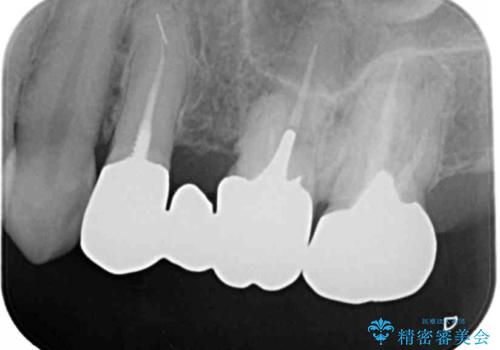

銀歯を除去し、土台の歯にに虫歯がないかを確認します。

今回は目立つ虫歯がなかったため、形を整えて白い被せものを装着しました。